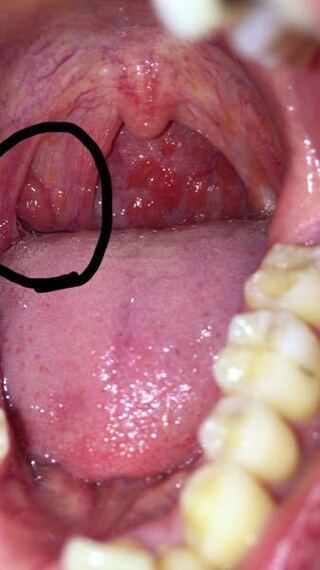

正常 な 扁桃 腺 画像

扁桃腺が炎症を起こしていますか それとも正常ですか 扁桃腺炎 Yahoo 知恵袋

これって扁桃腺ですか 正常ですか 返信お願いします Yahoo 知恵袋

この扁桃腺は正常ですか 喉の違和感 詰まっているような感じ Yahoo 知恵袋